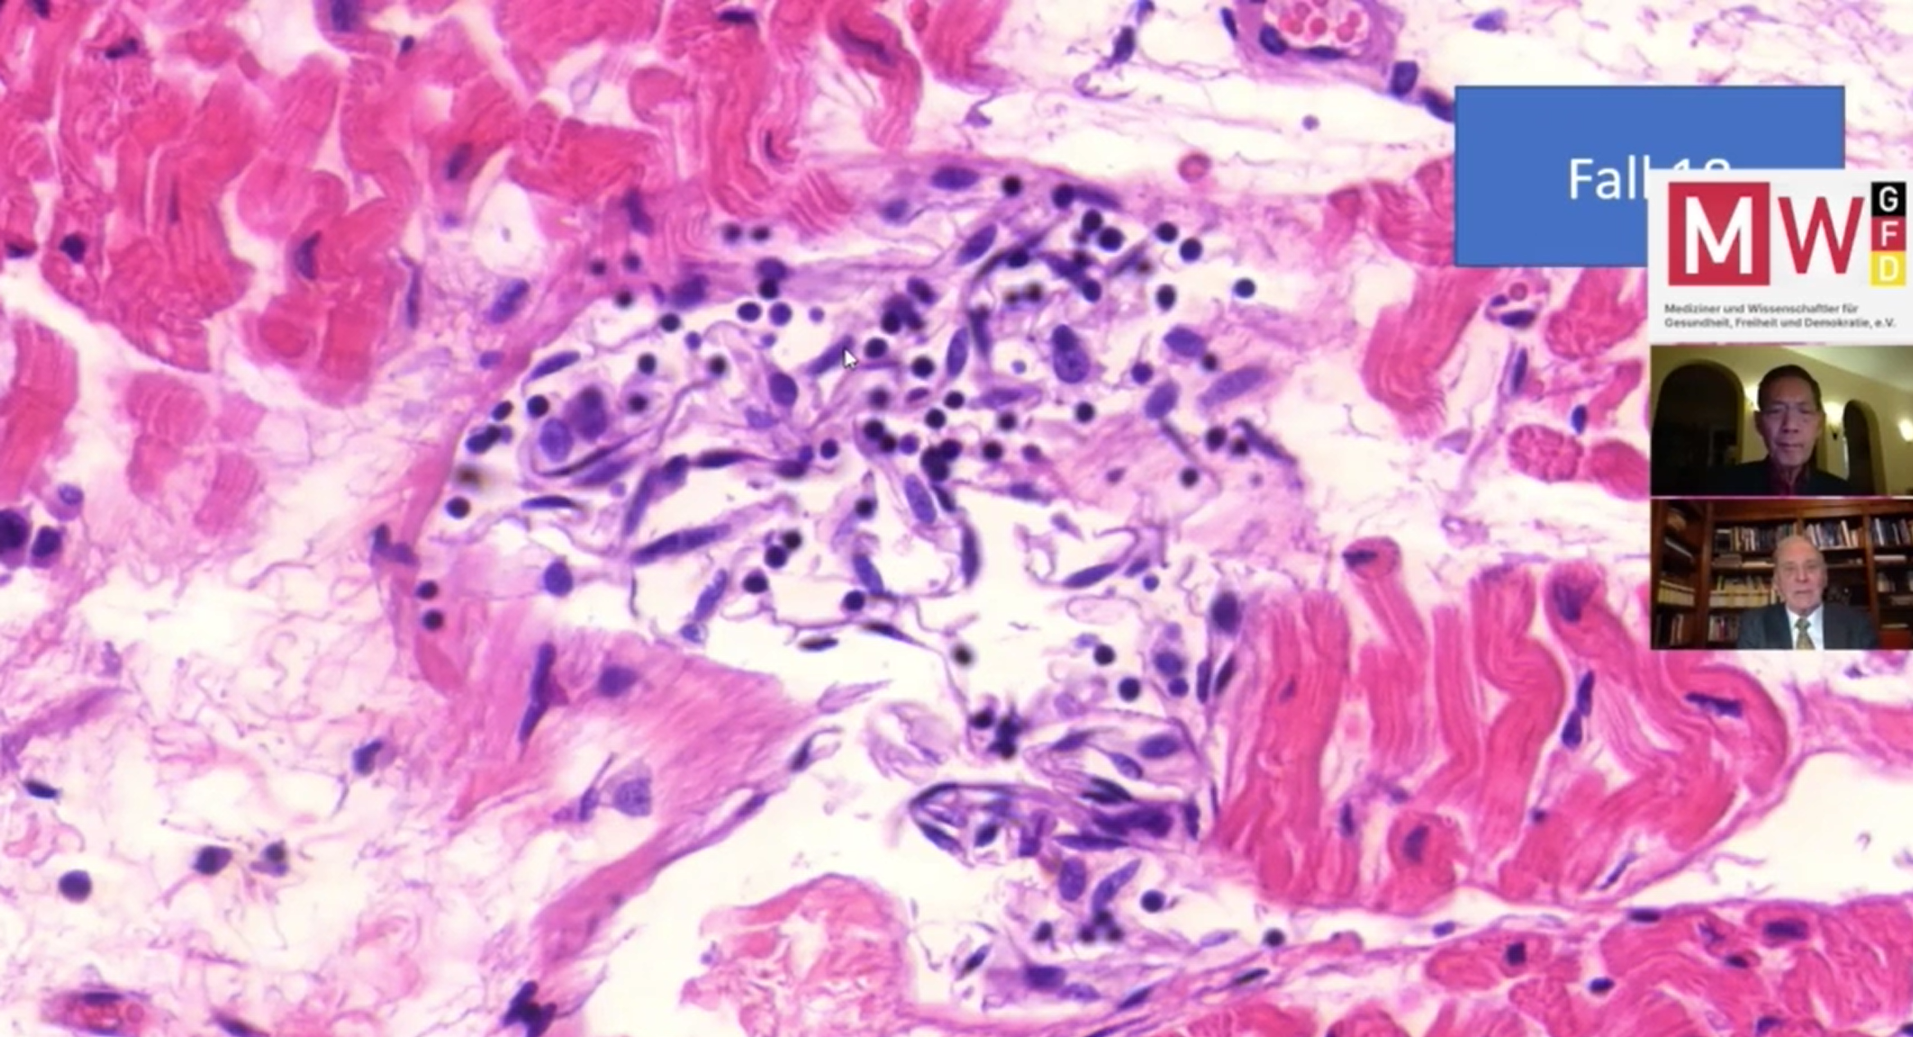

Professor Arne Burkhardt is a pathologist who has taught at the Universities of Hamburg, Berne and Tübingen (full credentials in the footnotes). Professor Burkhardt was able to conduct post-mortem examinations on 15 people who died after receiving covid-19 vaccinations.

The microscopic evaluation of the tissues showed an autoimmune attack on multiple organs. The most frequently affected organs were the heart (fourteen of fifteen cases) and the lung (thirteen of fifteen cases). Pathologic alterations were furthermore observed in the liver (two cases), thyroid gland ( two cases), salivary glands (two cases) and brain (two cases).

For example, the two images below show the microscopic evaluation of the small blood vessels of the heart. The endothelial cells that line the blood vessels have been heavily attacked and are inflamed.

Professor Arne Burkhardt in an interview said that in his forty years of experience he had not seen anything like these combinations of killer T lymphocytes throughout the body.

Dr. Sucharit Bhakdi and Professor Burkhardt have published an article summarising these findings on the Doctors for Covid Ethics website. They conclude:

“Histopathologic analysis show clear evidence of vaccine-induced autoimmune-like pathology in multiple organs. [This] must be expected to very frequently occur in all individuals, particularly following booster injections…

Beyond any doubt, injection of gene-based COVID-19 vaccines places lives under threat of illness and death. We note that both mRNA and vector-based vaccines are represented among these cases, as are all four major manufacturers.”